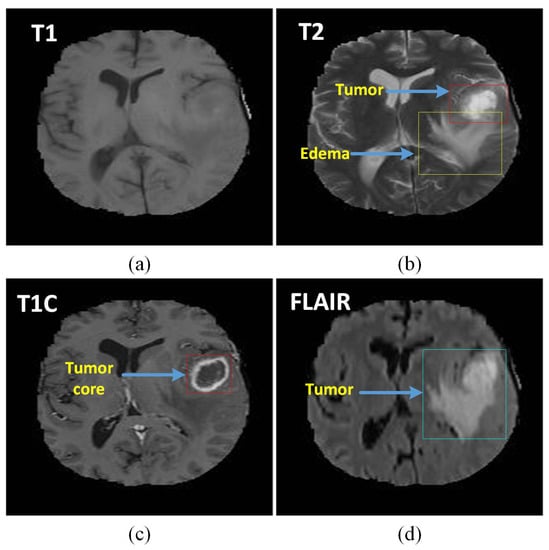

4. Data Set and Methodology